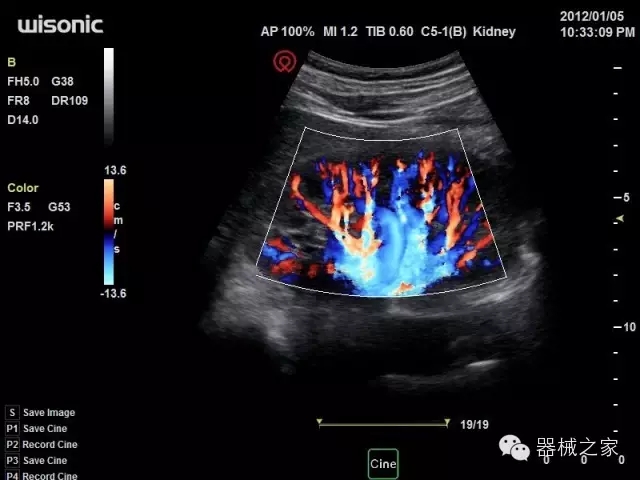

臨床圖片賞析

產(chǎn)品特點

優(yōu)異的成像技術

·亞陣元技術:獨有的亞陣元技術,對獨立晶片做二次切割,減少旁瓣偽像,增加臨床診斷的準確性;

·μ-Scan微米成像技術:開立獨有的μ-Scan技術,還原出真實細膩、層次對比優(yōu)異的二維圖像;

·倒相諧波成像技術:倒相諧波技術在去除基波信號的基礎上獲取兩倍二次諧波信號,提高組織圖像的對比分辨力;

·智能微血流成像技術:智能微血流捕捉技術可以提取出隱藏在背景噪聲中的弱血流信號,大大提高低速血流的敏感性;

全面的臨床解決方案

超聲科常規(guī)領域應用

·移植S40高端臺式彩超高端平臺技術,滿足超聲科腹部、淺表、婦產(chǎn)科、心血管、肌骨等應用,提供超聲科完美解決方案;

·實時的彈性成像技術:提高了小器管(乳腺,甲狀腺、淺表軟組織腫瘤等)疾病鑒別診斷;

·IMT血管內(nèi)中膜自動測量:為血管性疾病評估提供了有效的評估手段;

·心功能綜合指數(shù)(TEI指數(shù)):用于左、右心室整體心臟收縮舒張功能評估的測量方法;

·全方位可調M型:有利于更好的觀察心腔大小及室壁階段性運動的異常情況;

·組織多普勒成像(TDI):TDI可定量評價心肌運動,判斷是否有局部病變,還可評價早期的舒張功能;

·高效3D/4D成像技術:高速的4D幀頻,豐富的3D成像模式,智能斷層切片功能;

POC領域解決方案

·外觀小巧;

·穿刺增強技術:可有效提高進針區(qū)圖像分辨率,提高進針亮度,全面提高一次性穿刺的成功率;

全面的術中探頭解決方案

·小凸探頭:開放性手術,實時監(jiān)測病灶位置,提高手術成功率,可應用于麻醉科、肝膽外科、腫瘤外科、神經(jīng)外科、泌尿外科等手術;

·L型線陣探頭:高分辨率圖像,清晰顯示病灶位置,提高手術成功率,可應用于麻醉科、胸外科、肝膽外科、腫瘤外科、神經(jīng)外科、泌尿外科等應用;

·MPTEE:經(jīng)食道探頭術中監(jiān)測,可測量心臟前負荷(左室舒張末期大小、右房大?。⑿呐叛?、后負荷、收縮功能、室壁運動分析、肝靜脈血流(與中心靜脈壓相關)等,術后還能及時評估手術效果評估;

·獨有的大角度及實時溫控技術,能同一切面顯示宮頸及宮體,有效減低了患者的痛苦,及保護粘膜保證了醫(yī)療安全;

高效的人機工程學設計

·15‘’高清醫(yī)用顯示器;

·內(nèi)置雙探頭接口;

·可升降臺車,1拖3探頭擴展器;

·m-Tuning一鍵優(yōu)化;